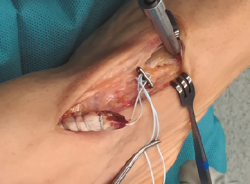

Figura 2. Tendón tibial anterior rescatado tras apertura del retinaculum superior.

Se prosigue con una disección de partes blandas, identificando y protegiendo las terminaciones nerviosas superficiales hasta llegar al retinaculum extensor, realizando apertura del mismo hasta encontrar el muñón proximal ascendido del TA (Figura 2). En los casos evolucionados o crónicos se puede apreciar una fibrosis que ocupa el compartimento del TA.

Figura 3. Sutura del tendón tibial anterior con hilo no absorbible.

Se realiza una disección y liberación del TA, resecando la porción distal más degenerada del tendón en forma de punta para introducirlo a través del túnel óseo con mayor facilidad y se sutura con hilo no absorbible (Figura 3), que después pasaremos a través de los orificios de la placa metálica de anclaje extracortical (de dimensiones de 4 × 12 mm).